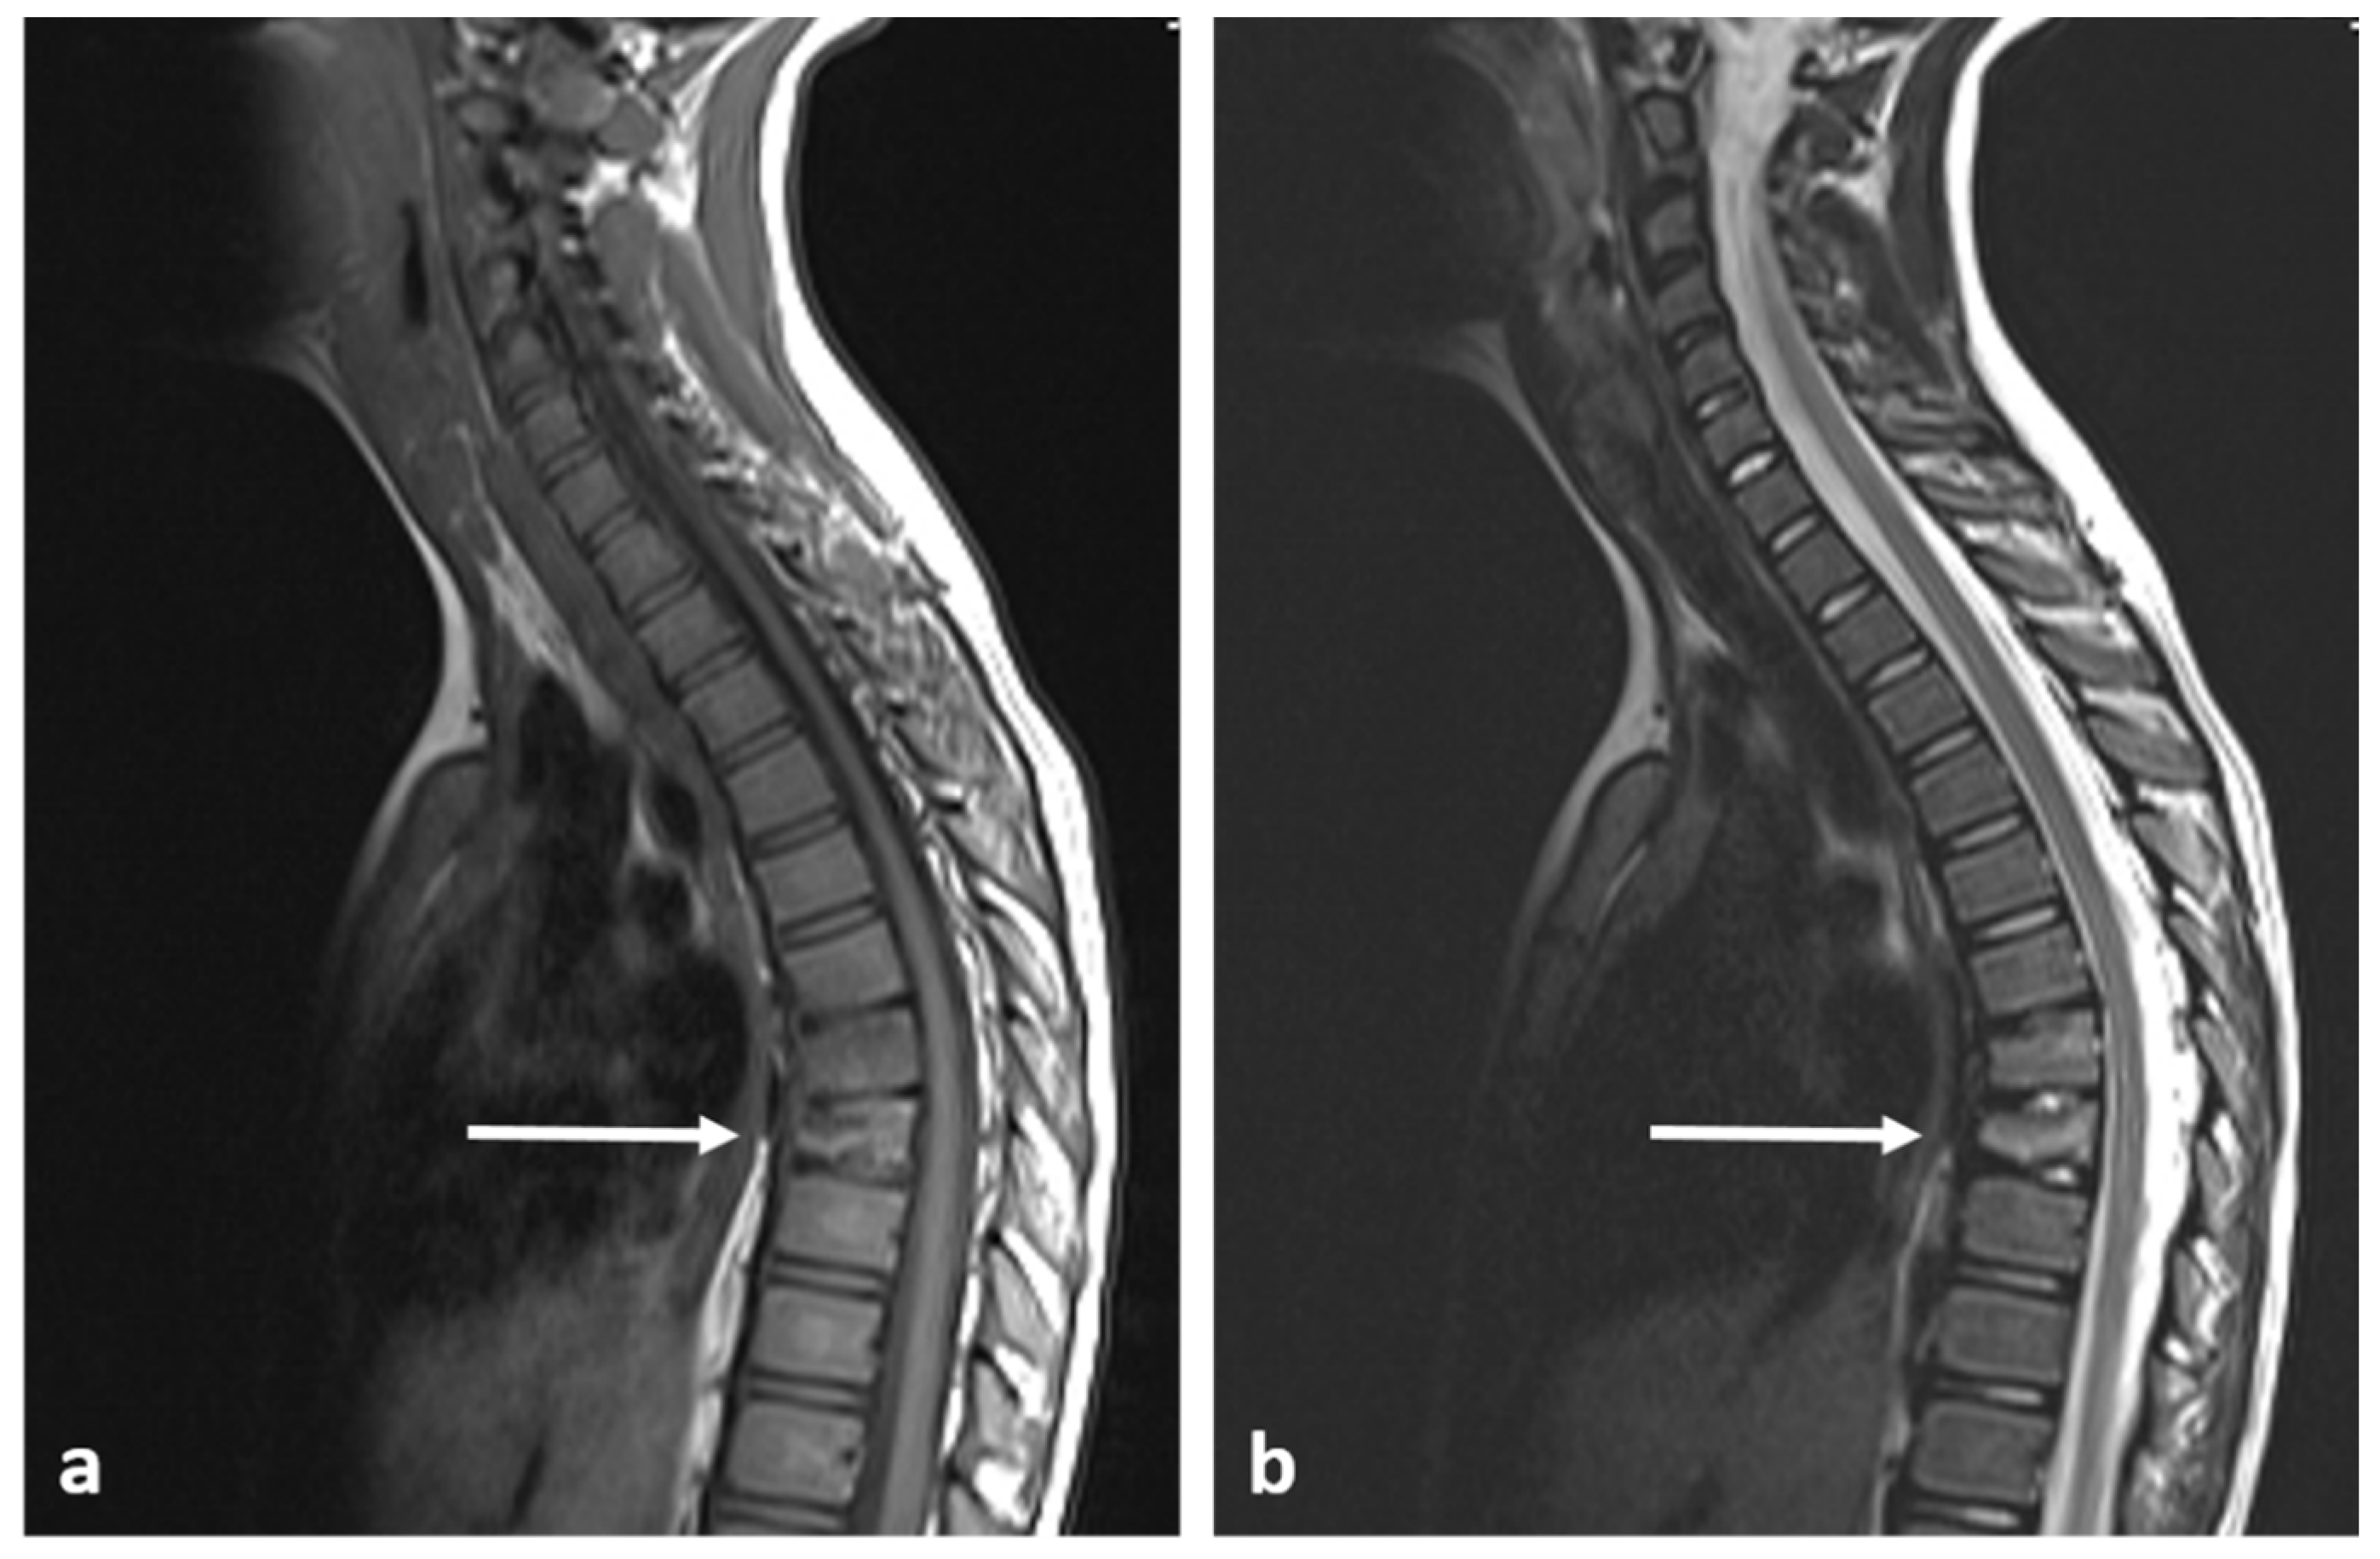

| Haemangioma | Honey comb appearance. ‘Corduroy’ and ‘polka dot’ signs. | Usually T1 and T2 hyperintense due to fat content. Signal drop out >20% on out of phase chemical shift imaging. |